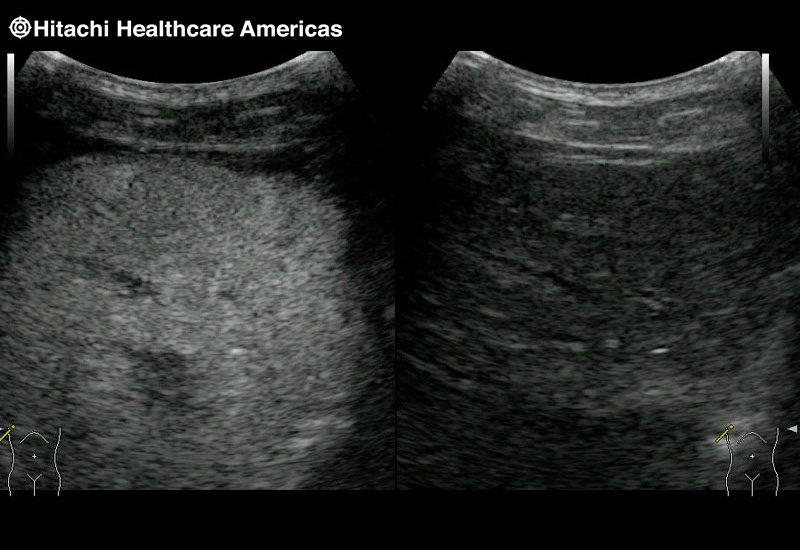

Reliable and Flexible Systems

Fujifilm Healthcare designs products with speed, comfort and quality in mind.

The Arietta 65 has many advanced and unique probes that fully cover the expanding range of procedures that benefit from ultrasound guidance.

The Arietta 65 has many advanced and unique probes that fully cover the expanding range of procedures that benefit from ultrasound guidance.